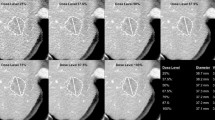

CT evaluation by radiologists

Up to five sharp and well-defined hepatic target lesions—according to RECIST standards—were chosen, including hyperdense lesions in the arterial phase and hypodense and heterogeneous lesions in the portal-venous phase. The following were measured by an experienced radiologist to assess RECIST und WHO criteria (Fig. 1):

- R1 :

-

Longest axial diameter

- R2 :

-

Longest diameter perpendicular to R1 in the same image

- R3 :

-

Product of R1 and R2 (R1 × R2)